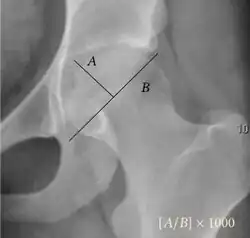

| Reimer's migration index[9] | ![]() |

The percentage of the femoral head that lies outside of the acetabular roof. It is also called the femoral extrusion index. | <25% |